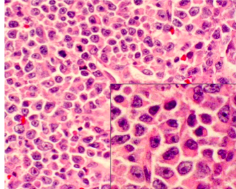

Non-Hodgkin’s Lymphoma pathology

-diffuse sheet of inflammatory cells

*Histology: sheets of plasma cells in various degrees of differentiation

multiple myeloma histology

*sheets of plasma cells in various degrees of differentiation

*plasma cells have eccentric nucleus, perinuclear halo, clockface nucleus